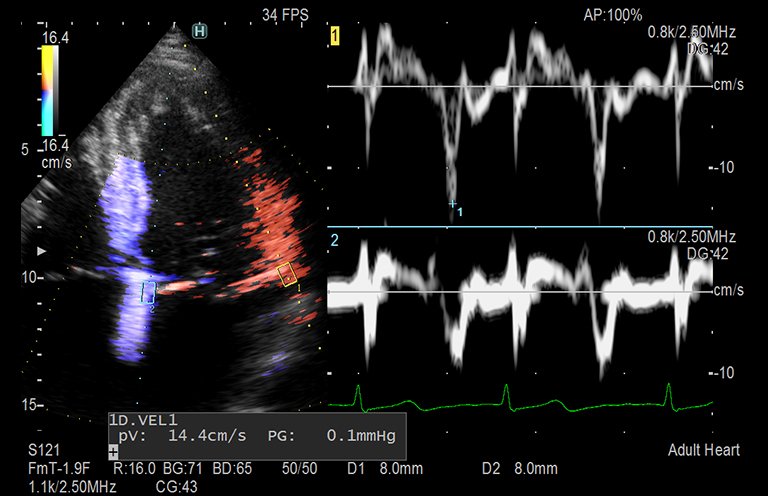

Aplicación: Cardiología

Función/análisis: Doppler de doble puerta

Comentarios: Corazón